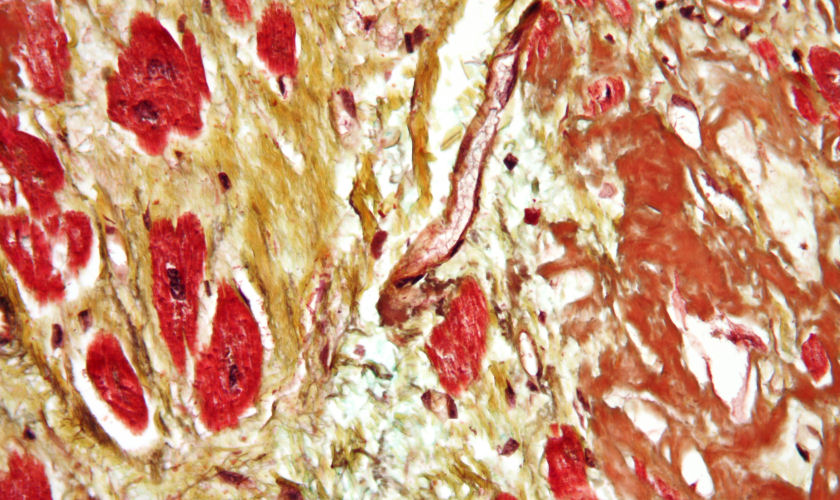

back cardiac amyloidosis

Source: Cardiac amyloidosis very high mag movat.jpg